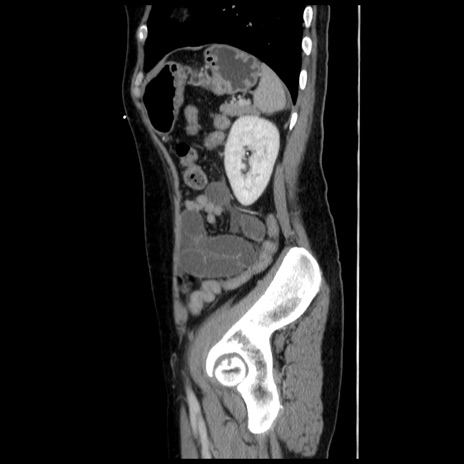

症例10(矢状断像)

【症例】 50歳代女性

【主訴】 腹痛

【現病歴】前日生レバーを食べた。今朝に排便あり。 昼前に突然発症の腹痛を生じ、当院救急外来を受診した。

【既往歴】 子宮筋腫にてで子宮全摘後

【身体所見】 意識清明、腹部:平坦、軟、下腹部やや左を中心に圧痛・反跳痛あり、筋性防御あり

【データ】WBC 7800、CRP 0.07